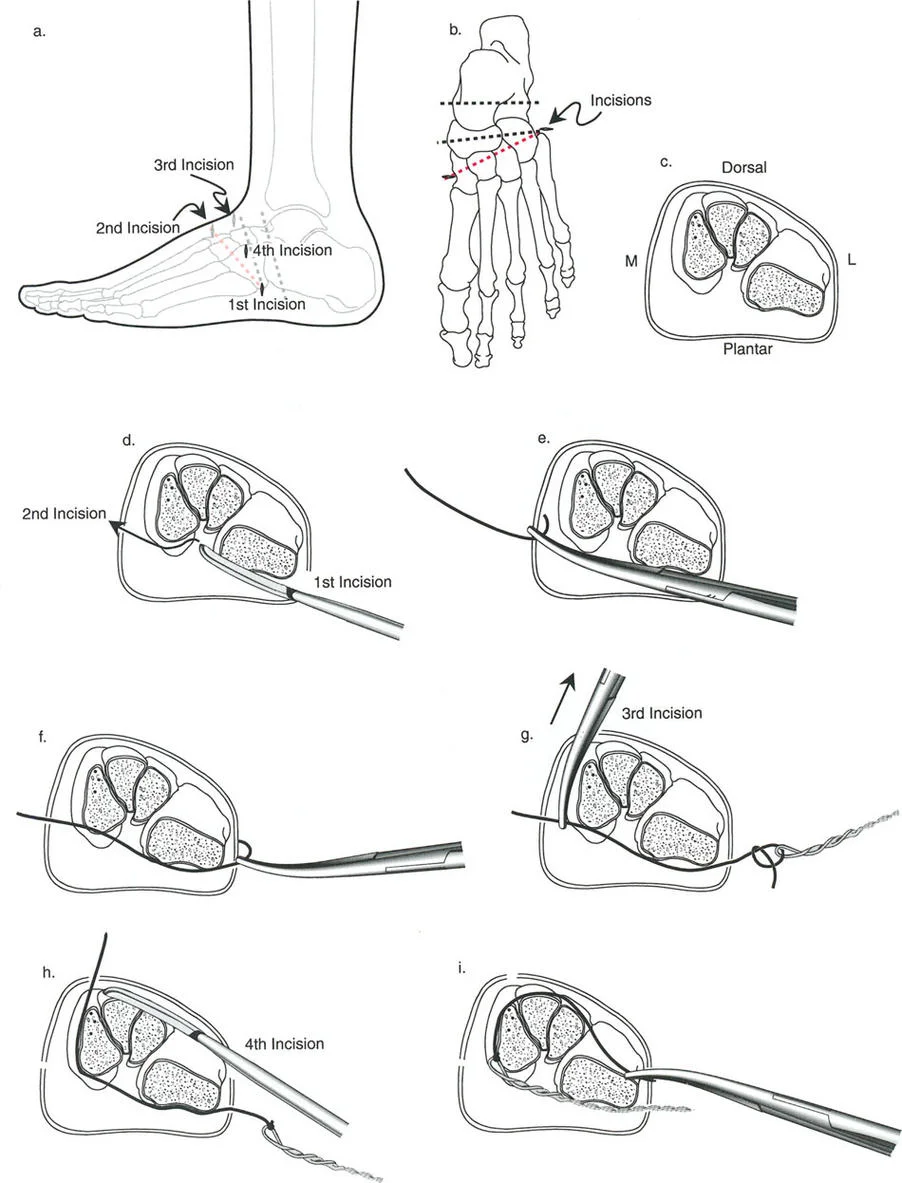

قيود الأسلاك والدبابيس في القاعدة 2

لتحقيق هذه الترجمة الضرورية والمقصودة بسلاسة باستخدام إطار دائري كامل الأسلاك، يلزم استخدام أسلاك الزيتون المعاكسة (counter-opposed olive wires). تعمل أسلاك الزيتون كقوى سحب ديناميكية، تسحب قطعة العظم على طول الحلقة أثناء فتح المفصلات. بدون أسلاك الزيتون، سيبقى العظم ثابتًا بينما تتحرك الحلقة عبر الأنسجة الرخوة، مما يسبب نخرًا شديدًا في الجلد.

على العكس من ذلك، إذا تم استخدام دبابيس نصفية (مسامير شانز)، فإنها تقيد العظم بطبيعتها بالحلقة. نظرًا لأن الدبابيس النصفية هي أذرع صلبة (مثبتة من طرف واحد بالحلقة ومغروسة في العظم من الطرف الآخر)، فإنها لا تسمح للعظم بالانزلاق على طول محور السلك. هذا يجعل أسلاك الزيتون غير ضرورية للترجمة في منشآت الدبابيس النصفية، ولكنه يتطلب من الجراح التأكد من أن الدبابيس النصفية قوية بما يكفي (عادةً دبابيس بقطر 5 مم أو 6 مم مطلية بهيدروكسي أباتيت) لتحمل لحظات الانحناء الناتجة عن الترجمة.

نصائح جراحية للمنشآت القريبة من المفصل

| تقابل الأسلاك | استخدم ما لا يقل عن سلكين زيتون متقابلين لكل قطعة إذا كنت تتجنب الدبابيس النصفية. | الأسلاك الزيتون الفردية ستسبب قصًا ودورانًا غير مرغوب فيه حول محور السلك. |